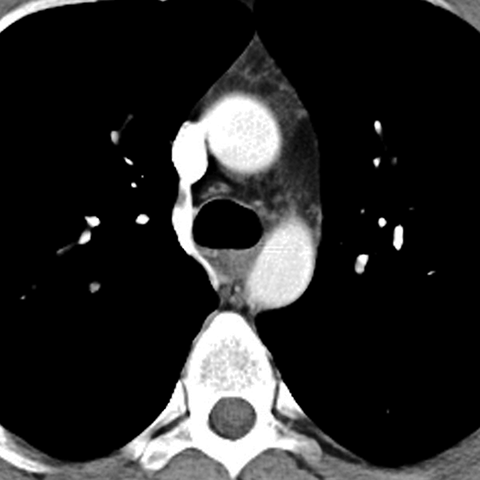

Normal Mediastinum (Axial CT) [3 of 5]